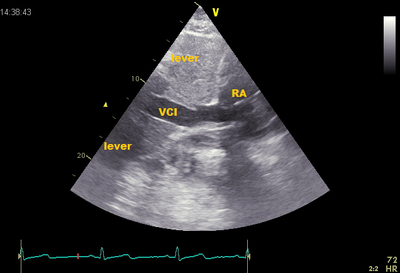

Echocardiographic view

Subcostale view M-mode collapse VCI

Because in most cases VCI is perpendicular to the beam in the ultrasound image running, the flow pattern of the hepatic vein viewed . This is the same as VCI, only the hepatic vein is parallel to the sound beam .